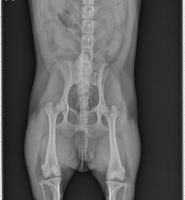

여름철이 되면 많은 여성분들이 다이어트에 대한 고민이 많아지게 됩니다. 짧은 옷을 입게 되면서 감추어두었던 살들이 드러나는 것에 대해서 스트레스가 많아집니다. 열심히 다이어트를 해보지만 복부나 허벅지, 팔뚝에 있는 살들은 여전히 빠지지 않습니다. 그래서 신체의 부위에 따라서 지방을 제거하는 흡입술을 받는 분들이 조금씩 늘어나고 있습니다. 대부분 짧은 옷을 마음껏 입고 싶어 하기 때문이라고 합니다. 하지만 시술 후에도 허벅지 지방흡입 흉터 때문에 걱정을 하는 분들도 있습니다.

지방흡입 흉터 관리는 수술 후에 의사의 지시에 따라서 해주시면 빨리 회복이 가능합니다. 체질에 따라서 흉터가 빨리 사라지지 않는 경우도 종종 있지만 시간이 해결을 해줍니다. 흡입을 하게 되면 절개를 하기 때문에 흉터가 생기는 것은 어쩔 수 없습니다. 또한 부위별로 절개를 여러 군데 해야 하는 경우도 있어서 흉터는 여러 군데 남게 됩니다. 예전에 시술을 할 때에는 지방을 골고루 제거하기 위해서 많은 곳을 절개했지만 현재는 절개하는 부위를 최소화하고 있습니다.

절개를 하는 부위도 가려질 수 있는 곳을 최대한 찾아서 절개를 합니다. 하지만 어쩔 수 없이 절개를 해야 하는 부위도 있기 때문에 흉터는 여러 군데 남게 됩니다. 멍이 다는 것은 몇 주 만에 대부분 사라지지만 흉터는 오래 갑니다. 물론 심하게 표시가 나는 것은 아니지만 흉터가 완전히 없어지기 위해서는 최소 1년 이상은 걸립니다. 그래서 시술을 받자마자 짧은 옷을 마음껏 입고 싶겠지만 참아야 합니다.